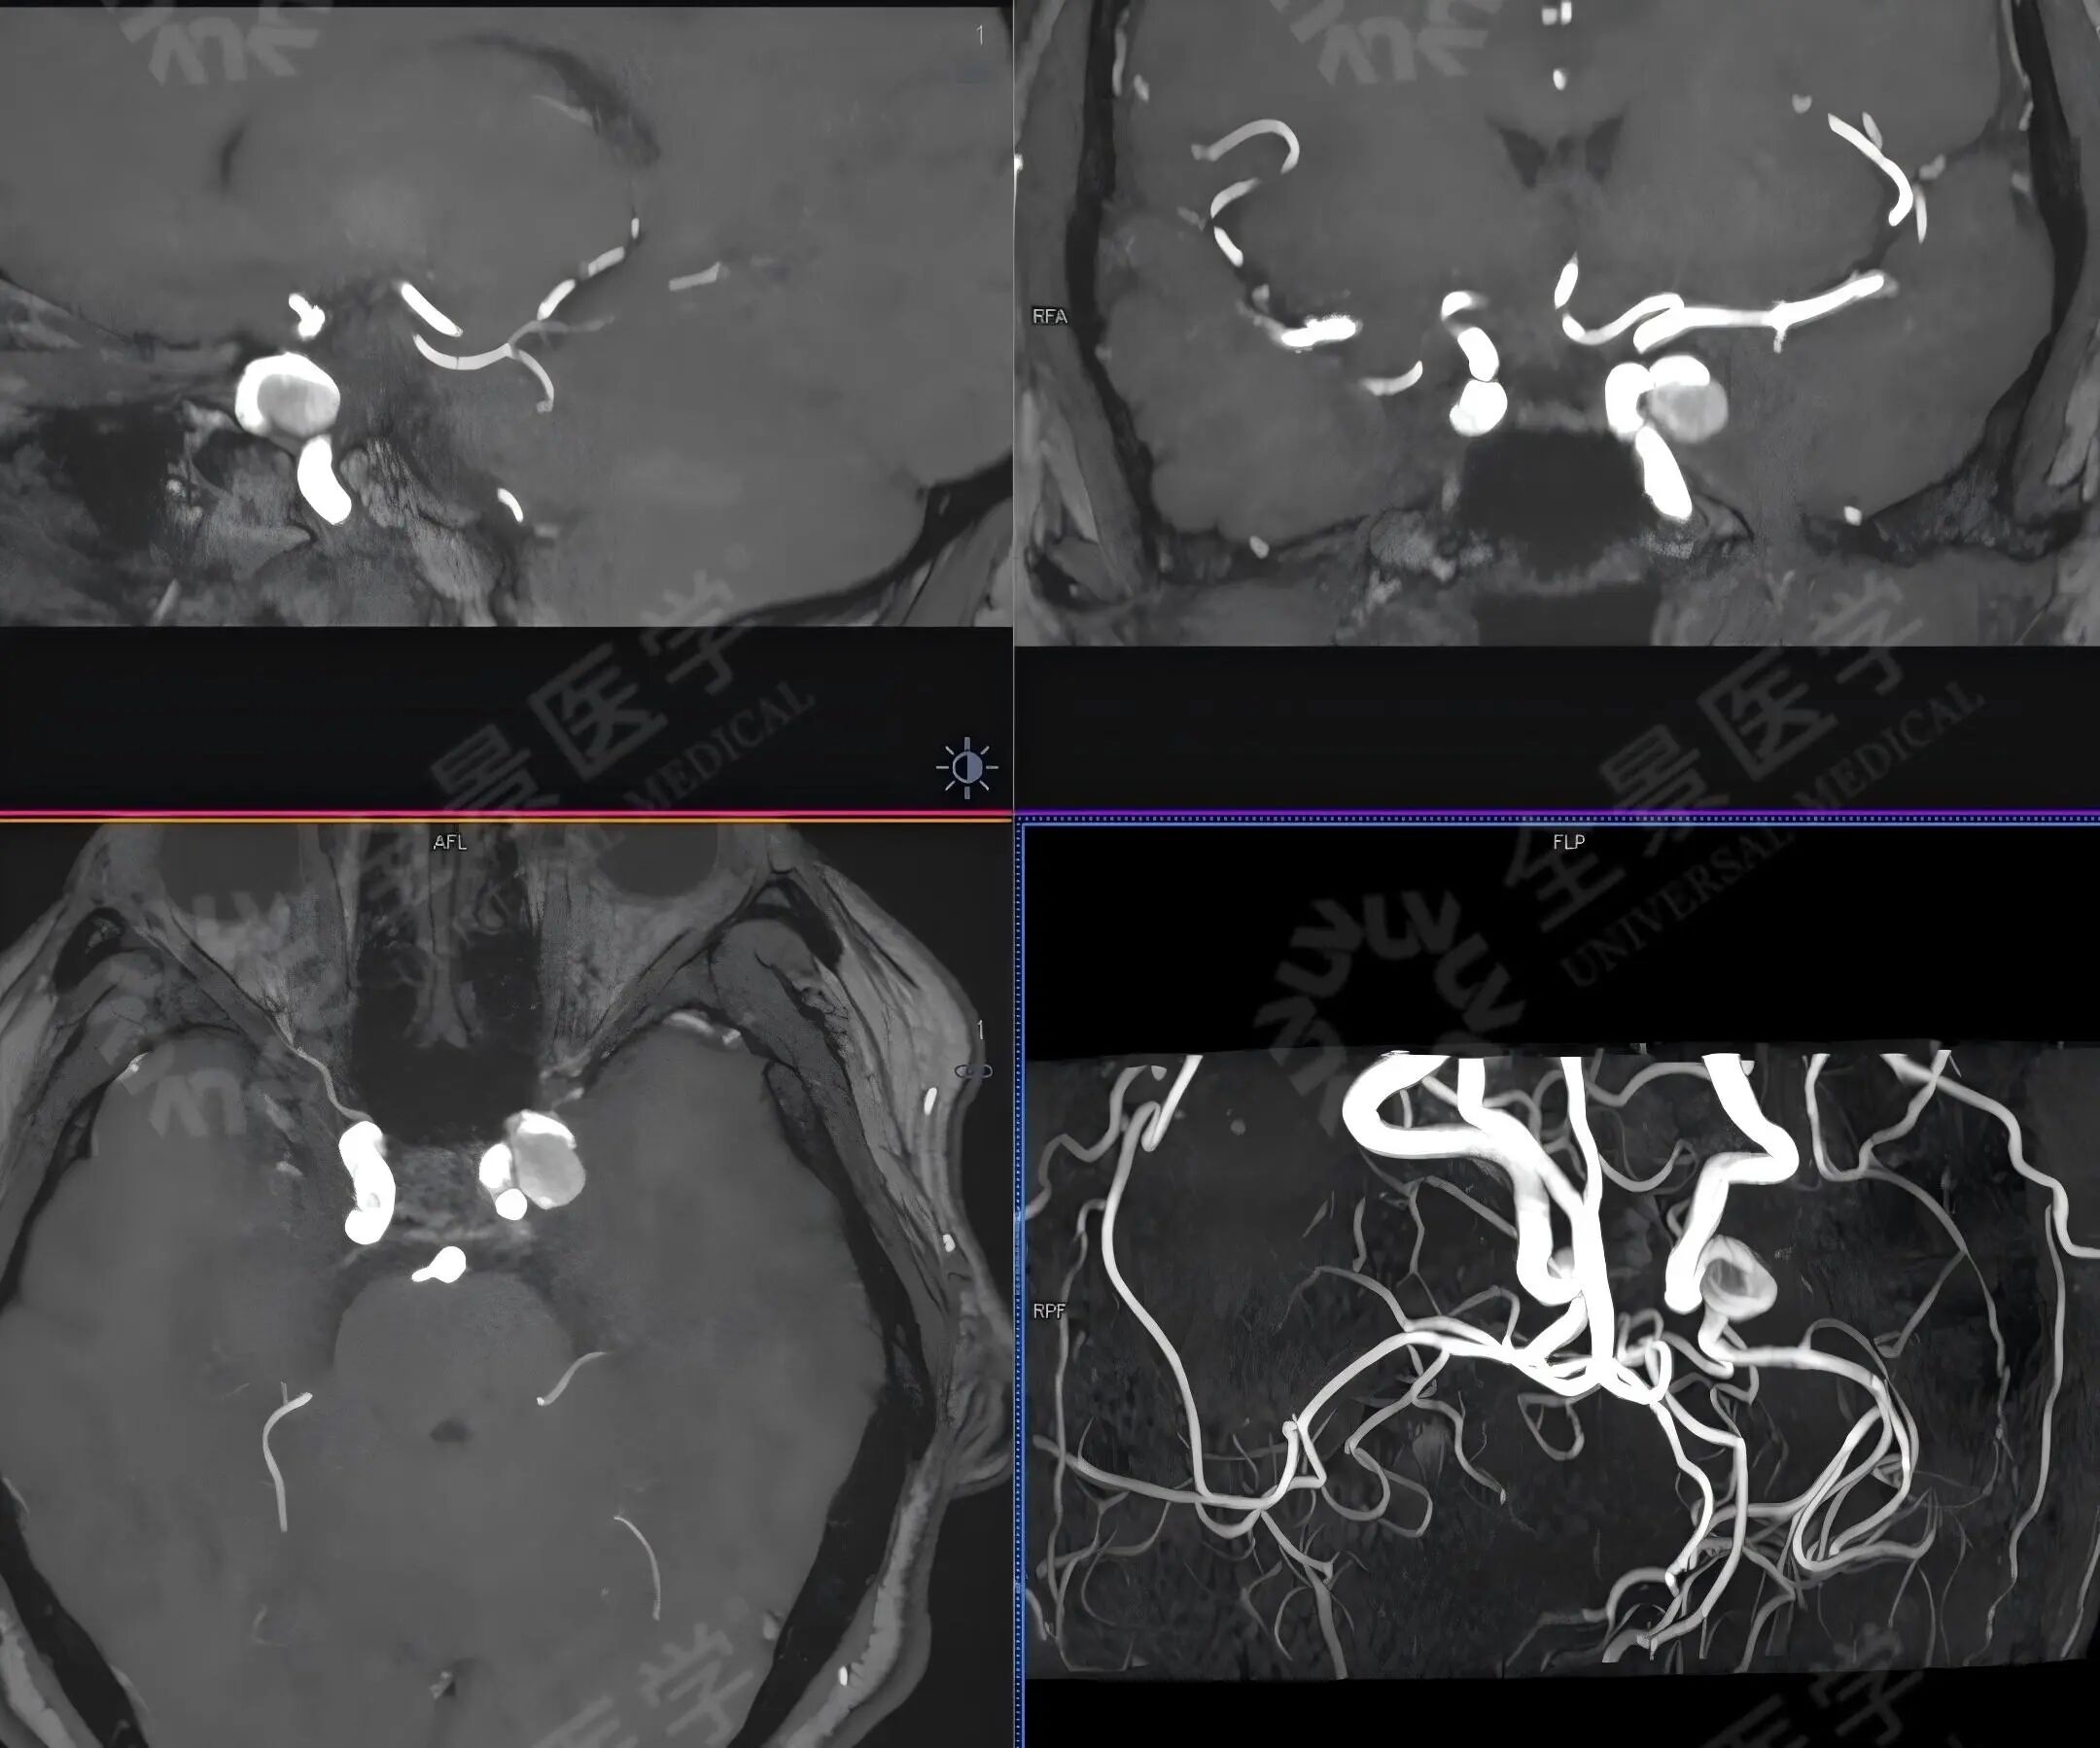

徐女士,48 岁,身体无明显不适,体检发现颈内动脉 C5 段大型动脉瘤。